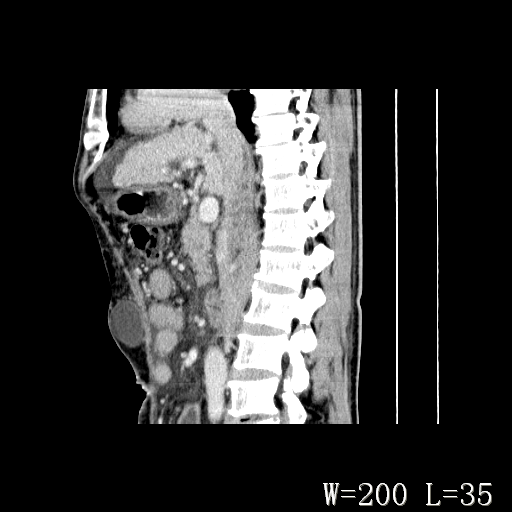

男,52岁,门脉高压断流术后1年,发现腹部肿物2月。

1)前腹壁中线区(脐上方)囊性占位性病变,考虑淋巴囊肿。2)腹水。